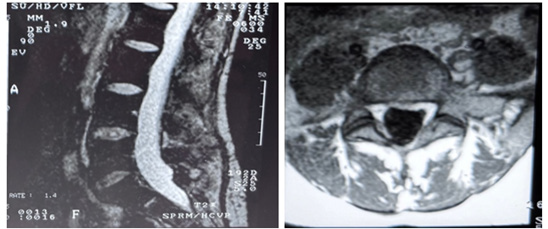

We present the case of a 40-year-old woman who presented with low back pain resistant to analgesics and rehabilitation. She was compensated and had excellent flexion and extension of her spine. The patient had a normal neurologic examination of the lower extremities. Radiographic evaluation revealed good sagittal and coronal balance, despite the co-existing mild thoracolumbar scoliosis. MRI showed Degenerative Disc Disease (DDD) at L4-L5 and L5-S1 (Figure 1A-B). She underwent a lumbar Total Disc Replacement (TDR) at L5–S1with the Charité III prosthesis and Posterior Transpedicular Dynamic Stabilization (PDS) with the Dynesys system at L4-L5 in 2001. Post-operatively, there was significant clinical improvement and the patient went back to work. In 2014, the patient complained of unremitting axial low back pain, aggravated by walking and sitting with increasing difficulty standing and looking straight ahead when walking. Concurrently, polyarthralgia and throcanteritis were also present. This motivated evaluation by Rheumatology for autoimmune disease screening which was negative. Despite being subjected to a new rehabilitation protocol, there was no clinical improvement. X rays showed a degenerative scoliosis with sagittal and coronal imbalance (Figure 2A-B) with multiple discopathies and syndesmophytes through the lumbar and thoracic spine. TDR and PDS were stable and in good position. MRI showed Dark Disc Disease at D11-D12 and from L1-L2 to L4- L5 (Figure 3A-B). The patient underwent a Transforaminal Lumbar Interbody Fusion (TLIF) at L3-L4, PDS removal and T4-L5 posterior fusion in November 2018. At the moment, the patient maintains reported significant improvement in her back pain and reduction in the requirement of analgesic medicines. Physical exam shows good spinopelvic mobility (Figure 4). Radiographs reveal good coronal and sagittal balance and satisfactory position of the total disc replacement and good fusion of the thoracic and lumbar spine proximally (Figure 5A-B) (Figure 6A-B).